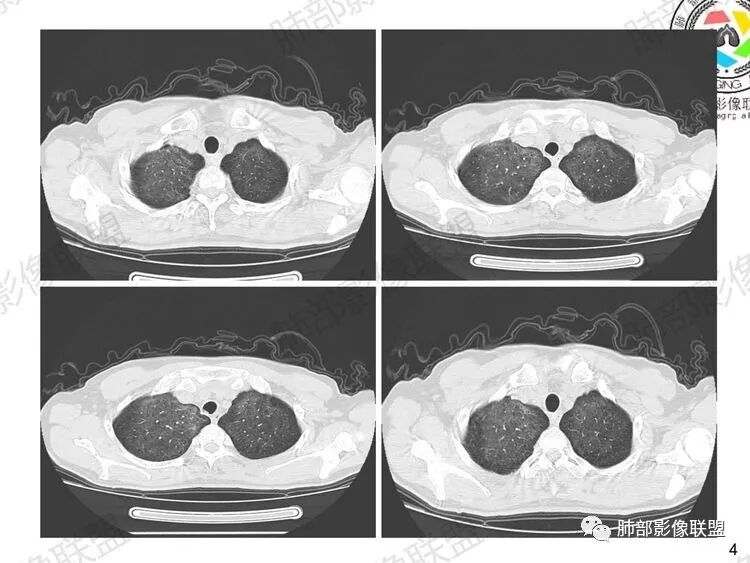

中期:孢子菌在肺泡腔内大量繁殖,引起炎性渗出及肺泡上皮增生,肺泡液内含有滋养体的嗜酸性渗出物及纤维蛋白和脱落的上皮细胞,Ⅱ型肺泡上皮细胞增殖修复受损的肺泡毛细血管间膜,肺间质内巨噬细胞、浆细胞和淋巴细胞增殖导致间质性肺炎,就是说有肺泡腔的密度增高,也有间质的增厚,整个肺受累区域密度都增高,形成以肺门为中心双侧对称的弥漫性磨玻璃样改变,胸膜下较少累及,呈典型的月弓征,采用积极的对症治疗后,大多数病变可吸收消失。

注意肺孢子菌肺炎的肺部影像看上去比较“干”,不会呈现重力趋势。肺血管影及支气管影都比较清楚,尤其是含气支气管影,常常会衬托得格外清晰。

1、双肺从中心向外周对称性弥漫分布的磨玻璃密度影,无重力分布特点

2、中内带分布为主,胸膜下较少受累,可见月弓征

结合患者症状典型的呼吸困难症状及影像学改变,临床症状轻,影像重,双肺从中心向外周对称性弥漫分布的磨玻璃影,无重力分布,胸膜下受累不明显(月弓征),呈典型的间质性改变,需要考虑肺孢子菌肺炎的可能,临床上需要结合有无HIV、使用免疫抑制剂病史、器官移植等免疫缺陷病史,还可以借助化验CD4细胞、LDH等进一步判断病情。